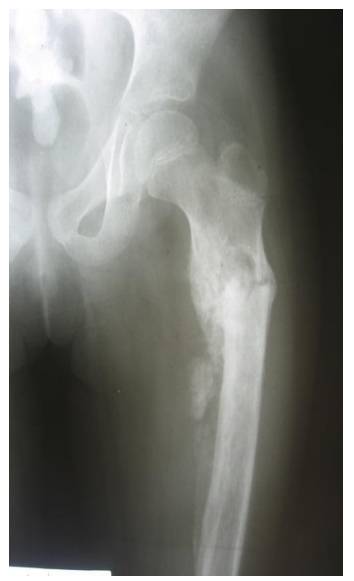

Ameliyat Öncesi: Röntgende proksimal femurda kırığa bağlı deformite, düzensizlik ve periost reaksiyonu görülmekte